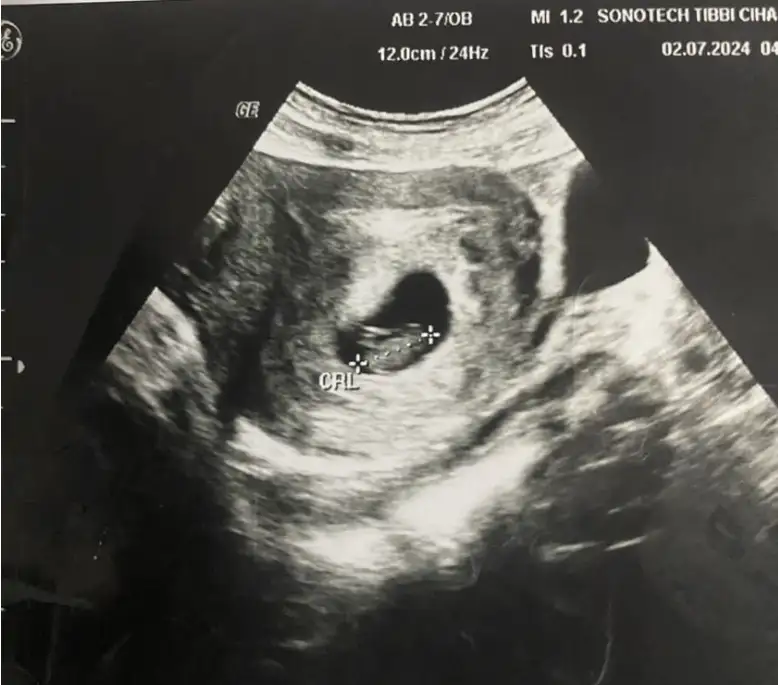

Kızlar bana da bakarmısınız rica etsem 🥲

8 hafta 3 günlük🥰❤️❤️❤️

Canım bana da bakar mısınız rica etsem 🥲

8 hafta 3 günlük karından bakıldı

Çok merak ediyorum 🥰❤️❤️❤️

Tam emin olamasam da kıza benzettim.

Bi tahmin sadece benim ki

Hayırlısı olur insallah